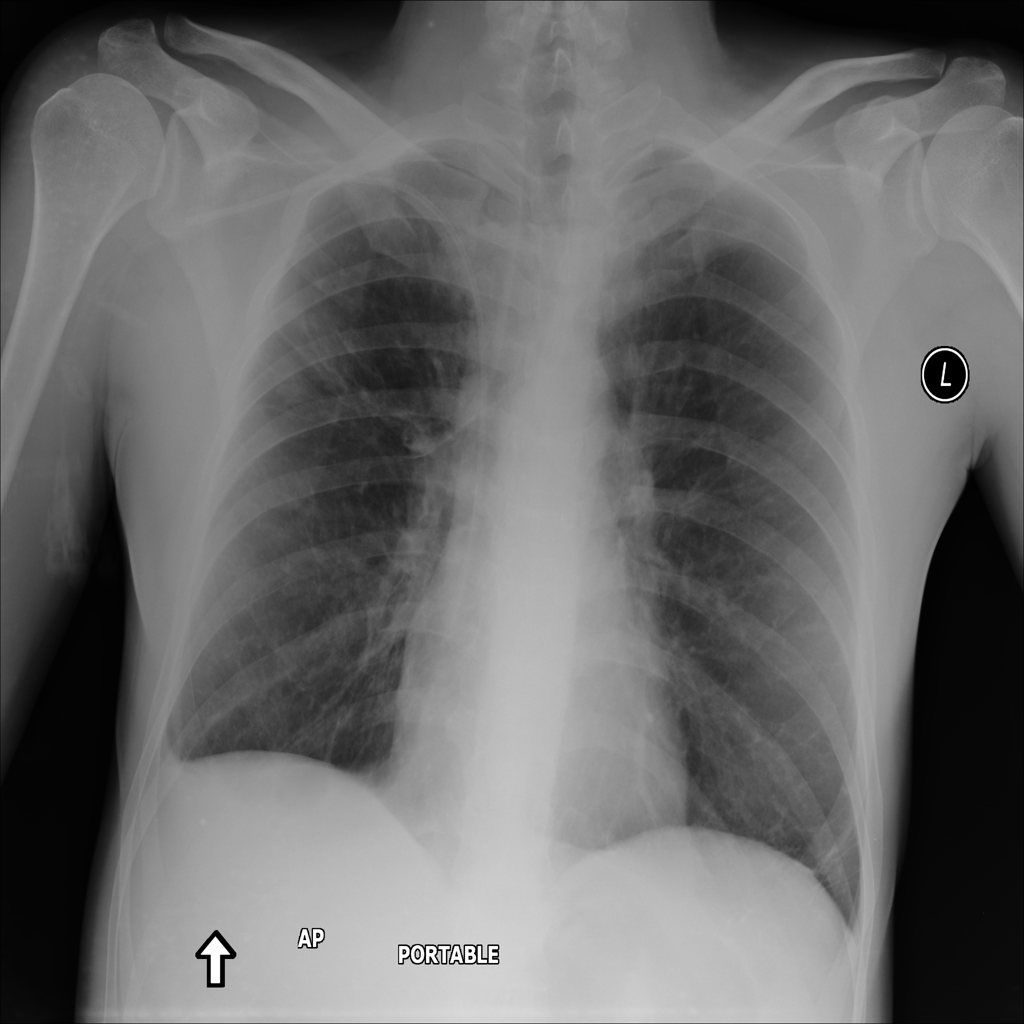

Showing up to 90 reference images for Nodule.

PAT-250B · IMG-000Nodule

PAT-250B · IMG-000

PA